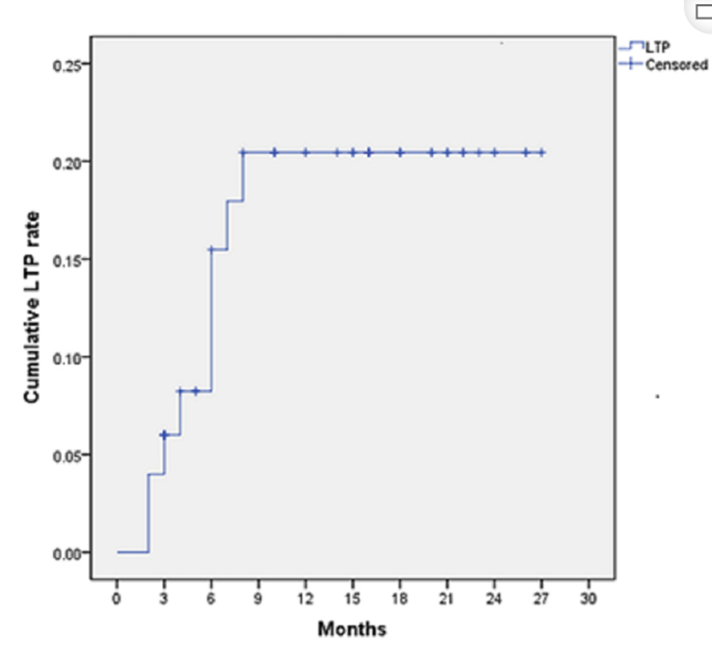

完全消融率为97%(66/68);2名患者均接受了额外的冷冻消融,随后实现完全消融。平均随访期为 12.8 个月(范围:3-27 个月)。所有患者均接受影像复查(CT 或 MRI)。11个病灶(16.2%)检测到局部肿瘤进展,6、12和18个月时的累积局部肿瘤进展率分别为4%、8.2%和20.5%。8例出现远处肝内或肝外病变的患者接受经动脉化疗栓塞、经动脉化疗栓塞加射频消融治疗或全身化疗。